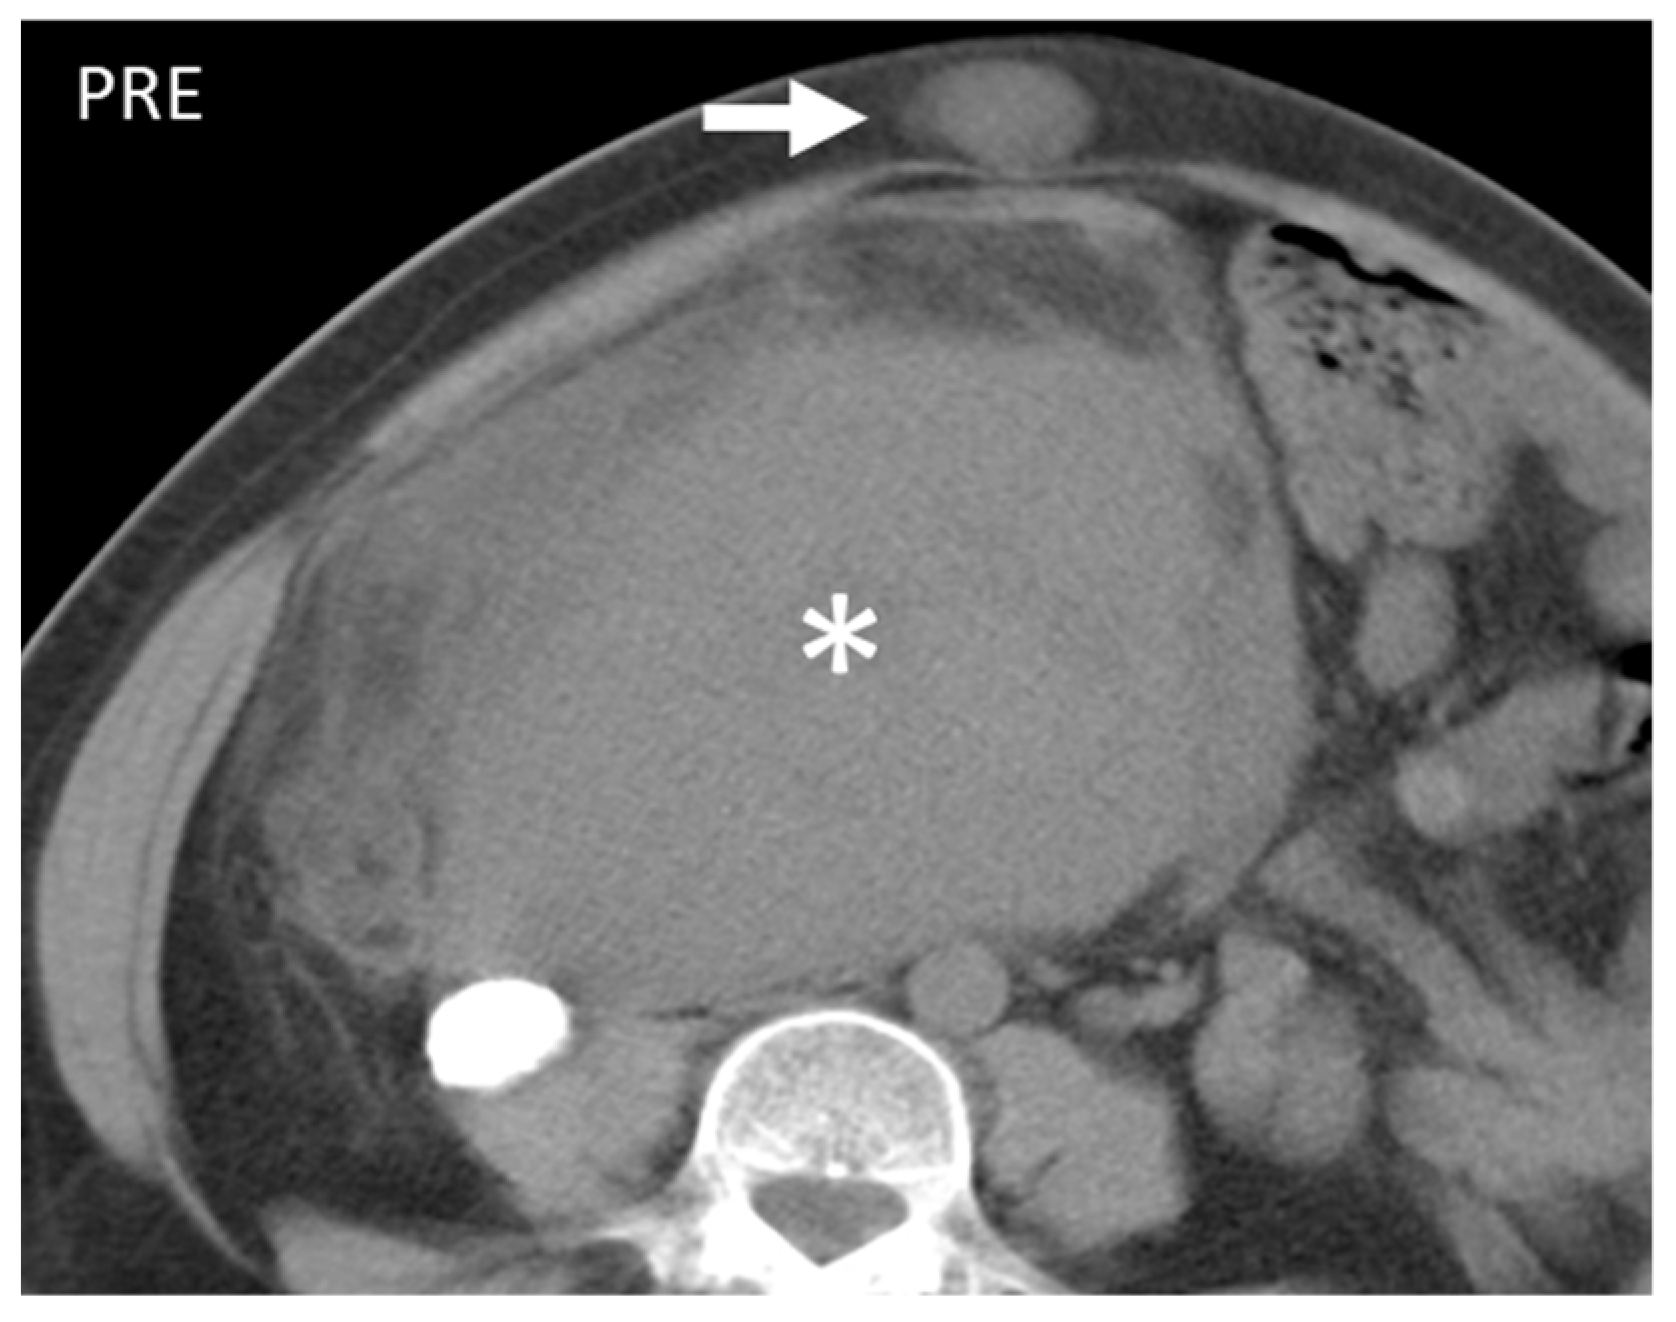

- Gastrointestinal Stromal Tumors (GIST): either primary (extraintestinal GIST, “EGIST”) [25,26] or secondary GIST of the abdominal wall are rare. When extended (>5 cm), GIST may have an aggressive behavior [25]. CT is the imaging modality of choice, showing heterogeneous vivid enhancement, and variable amount of necrosis. Peculiar findings include calcifications and cystic degeneration [27,28,29].